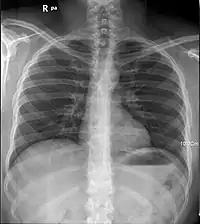

Rayos X del pulmón humano

Los rayos X son especialmente útiles en la detección de enfermedades del esqueleto, aunque también se utilizan para diagnosticar enfermedades de los tejidos blandos, como la neumonía, cáncer de pulmón, edema pulmonar, abscesos.